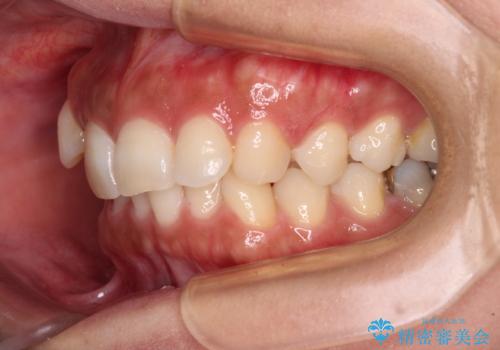

目立つ八重歯を改善 ワイヤー装置での抜歯矯正

- 目立つ八重歯を気にして来院された患者様です。

上顎小臼歯を抜歯するかどうか悩みましたが、八重歯の後方に失活歯があること、治療前に上顎正中が概ね人中に合っていることから、右上第二小臼歯を抜歯することとしました。